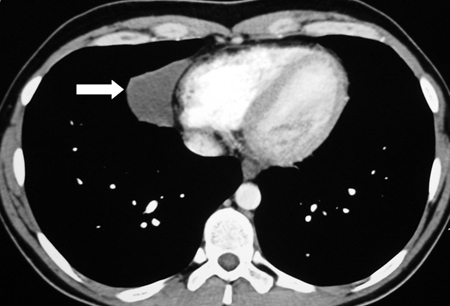

Imagem de tomografia computadorizada (TC) de cisto pericárdico

Dos acervos do Dr. Mario Gasparri e do Dr. Nicholas Choong